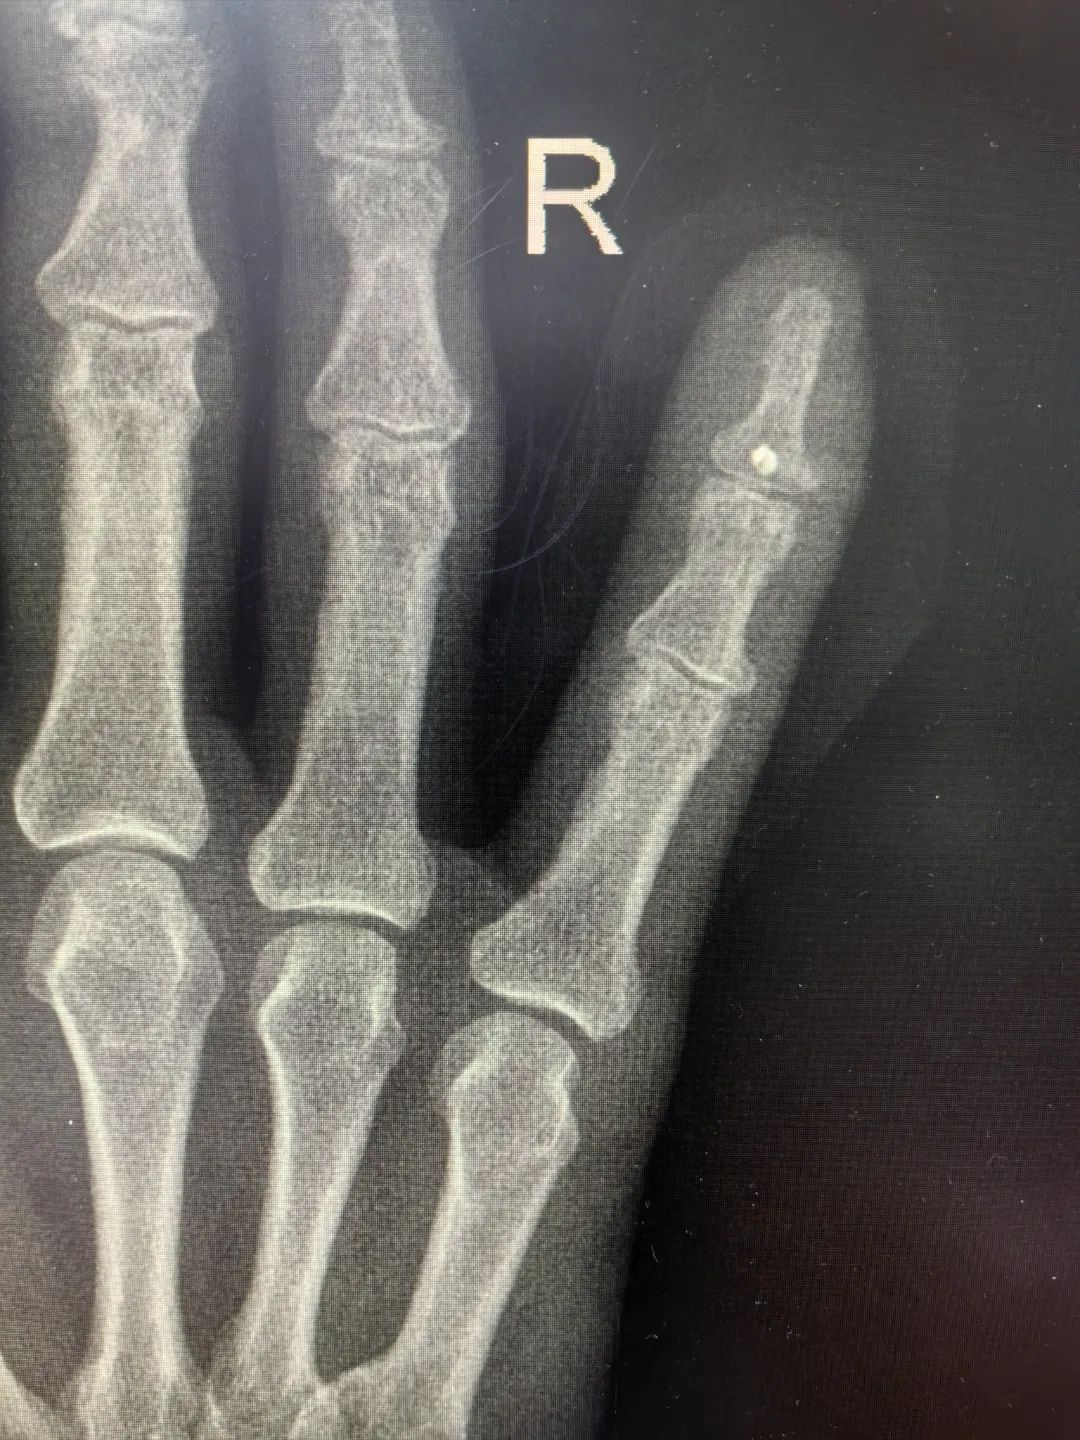

69歲的蔣先生一月前因意外撞擊導(dǎo)致右手小指受傷,當(dāng)時無明顯的皮膚破損但持續(xù)腫脹未愈,近日更是出現(xiàn)受傷手指屈曲無法伸直癥狀。經(jīng)影像學(xué)檢查確診為右小指遠(yuǎn)節(jié)指骨撕脫性骨折,患者慕名求診于我院骨科李強(qiáng)主任。經(jīng)過李主任詳細(xì)查體,明確可通過精細(xì)手術(shù)重建指骨功能。